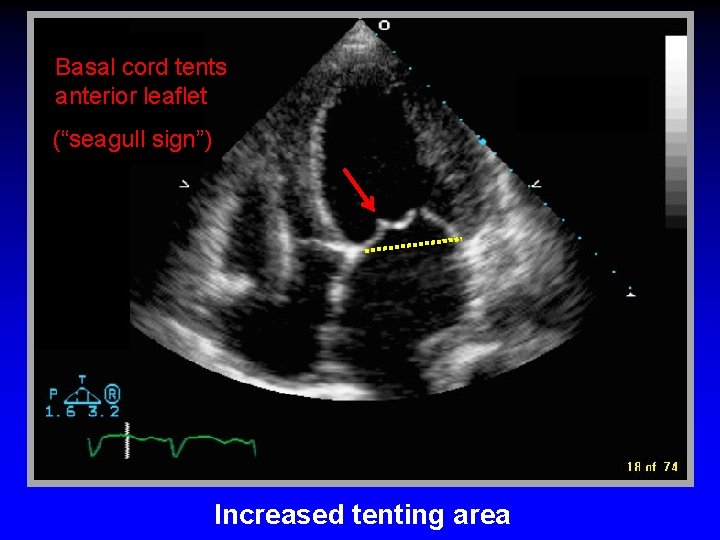

Basal cord tents anterior leaflet (“seagull sign”) Increased tenting area

Increased tenting area